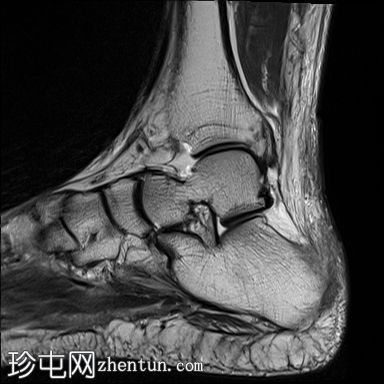

矢状位

T1加权像

跟腱完全撕裂,累及跟骨附着点,撕裂纤维近端回缩约38mm。回缩的肌腱明显肌腱病样改变和水肿。回缩肌腱下缘可见少量钙化碎片。

跟骨后侧可见骨髓水肿。

跟骨后侧可见皮质不规则,可能为肌腱附着点病变。

可见一小骨背侧骨刺。

可见较大的舟骨,大小约为 13 x 10 毫米。本次扫描未见明显的骨髓水肿。

可见腓骨,未见明显的骨髓水肿。

本病例显示跟腱近乎完全撕裂,累及跟骨附着点,撕裂纤维近端回缩。需行手术修复。放射科医生应注意撕裂部位和回缩程度。